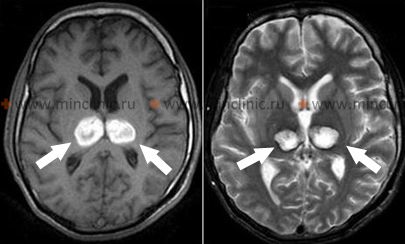

- თავის ტვინის მრტ: ყველაზე მგრძნობიარე მეთოდია, განსაკუთრებით თალამუსში, შუა ტვინსა და კეფის წილებში იშემიის აღმოსაჩენად. დიფუზიურ-აწონილი გამოსახულების (DWI) რეჟიმები კრიტიკულია მწვავე ინფარქტების დასადგენად დაწყებიდან წუთებში ან საათებში. მრტ-ს შეუძლია აღმოაჩინოს მცირე ლაკუნური ინფარქტები პენეტრირებადი ტოტის ოკლუზიისგან, რომლებიც შეიძლება გამოგვრჩეს კტ-ზე.

- თავის ტვინის კტ: საწყისი უკონტრასტო კტ აუცილებელია სისხლჩაქცევის გამოსარიცხად. ის ნაკლებად მგრძნობიარეა ვიდრე მრტ მწვავე იშემიური ცვლილებების აღმოსაჩენად, განსაკუთრებით უკანა ფოსოში ან ღრმა სტრუქტურებში, განსაკუთრებით პირველი 24 საათის განმავლობაში. ჩამოყალიბებული ინფარქტები მოგვიანებით ჩანს როგორც დაბალი სიმკვრივის უბნები.